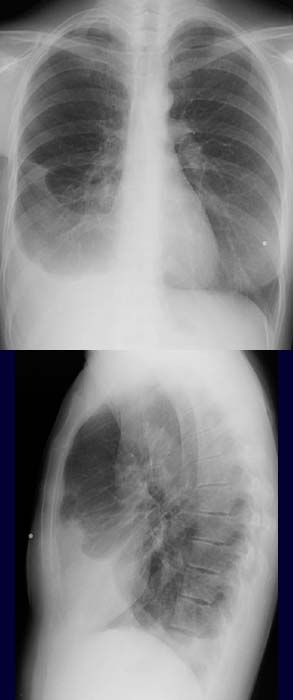

45-year-old female patient who had breast cancer two years ago.

Homogenous

shadow in the right costodiaphragmatic recess. Compare

the right with the left costodiaphragmatic angle. Homogenous

right paracardiac shadow in the right interlobar fissure stretching between

the middle and the lower lobes.

Take note of how the fluid

stretches in the interlobar fissure. Patient has had a right mastectomy -

compare the left

with the right rectangle. The nipple

marker on the left is not demonsrated on the right, likewise the breast

shadow on the left is

not seen on the right.

Pleural

effusion in the right costodiaphragmatic recess and

status post right mastectomy.

Trapped

effusion with dystelectasis of the right middle and lower lobes as a

result of compression.